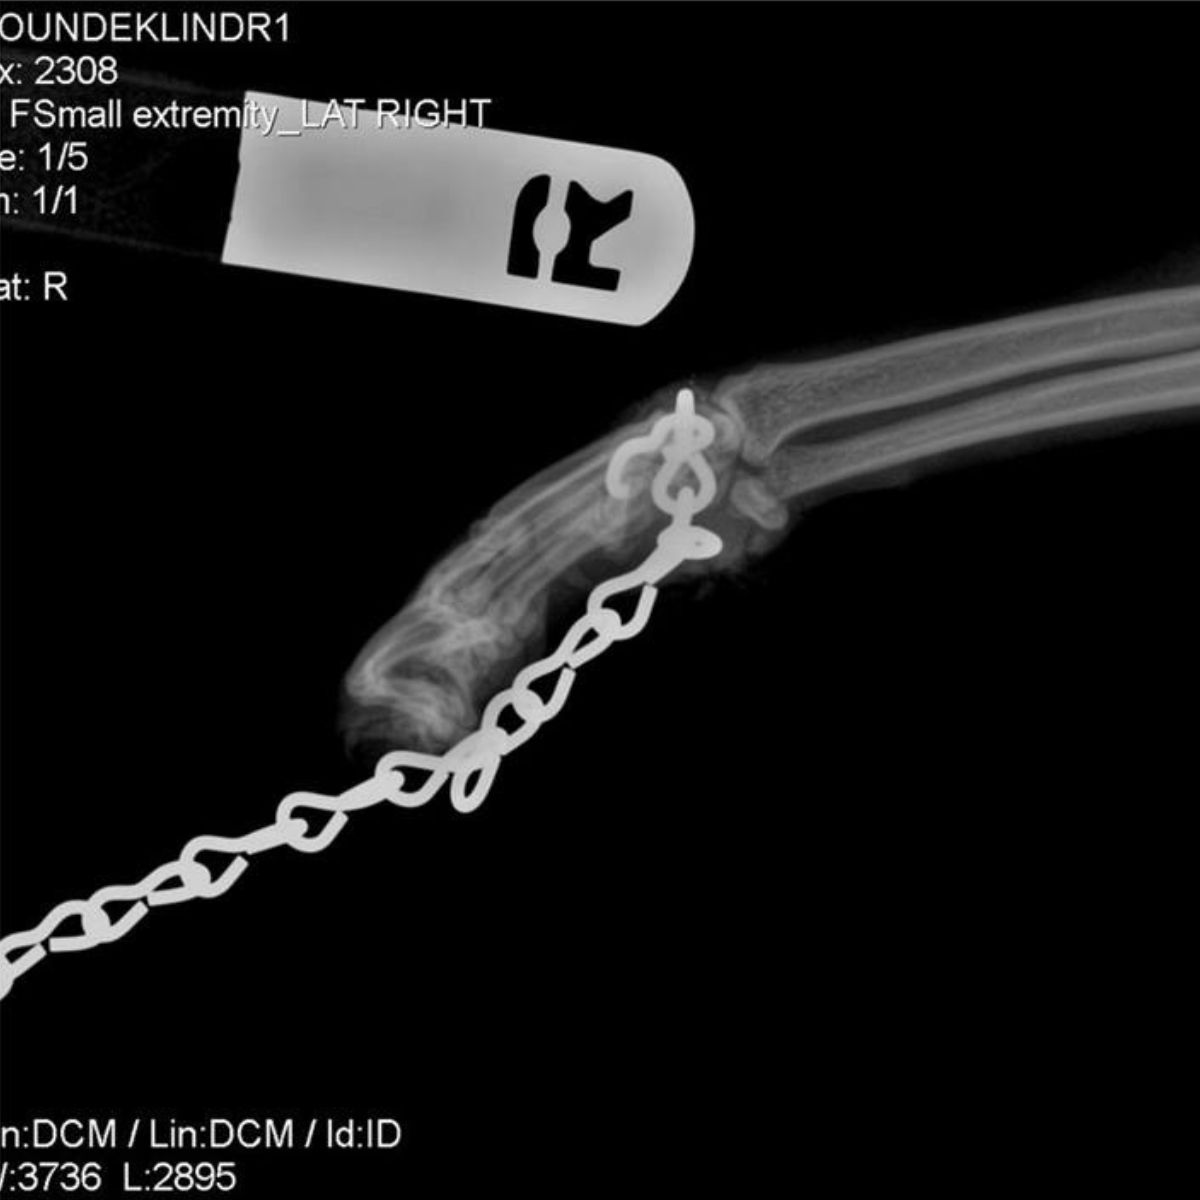

The situation reached its worst point when they fastened a heavy chain around her neck and tied it to her paw. This cruel act forced her to limp painfully, unable to walk normally or even rest her paw on the ground.

Ellen brought Ruby to VCA Bay Area Animal Hospital, where veterinarians examined her carefully. The chain had been on Ruby’s body for so long that it had become embedded in her leg, causing severe damage.

The situation was critical, and the vets warned that amputation might be necessary if they couldn’t remove it safely.

Still, the team refused to give up. After a careful and delicate procedure, the vets were able to remove the chain. Ruby’s life, and her leg, were saved. Everyone breathed a sigh of relief, but her journey to healing was only beginning.